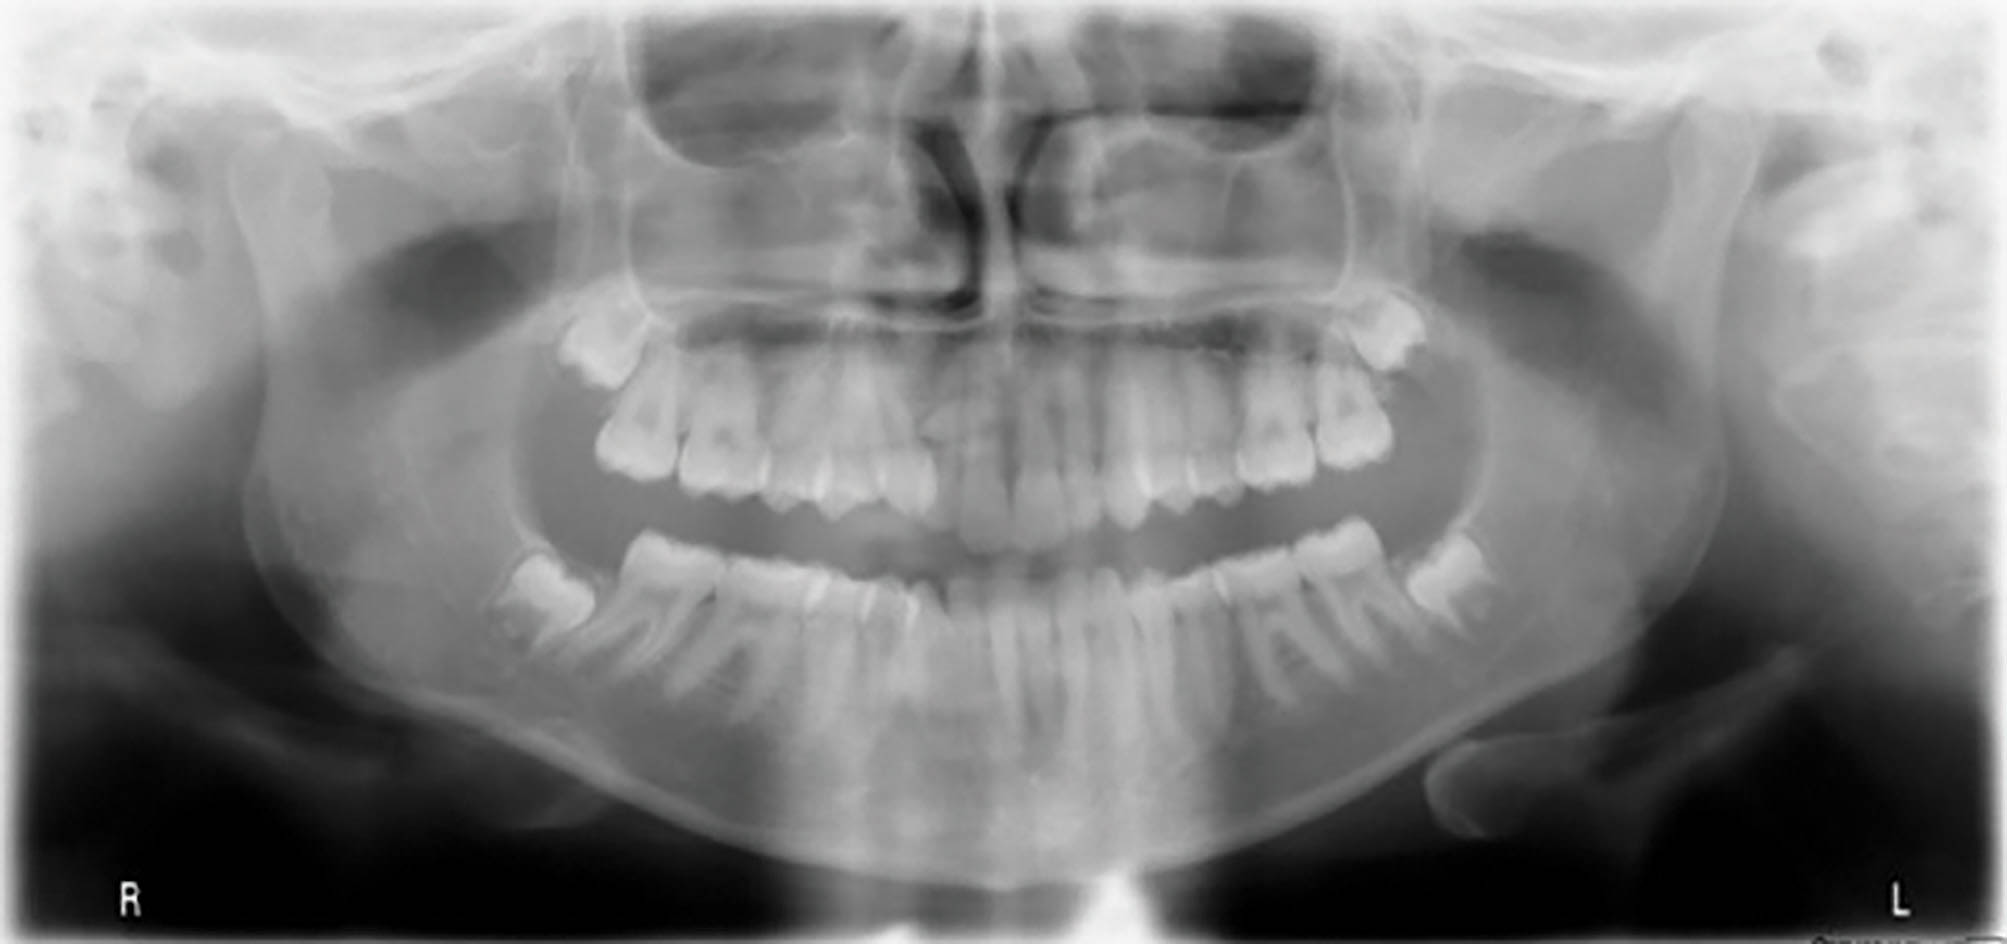

یک بیمار ۱۴ ساله دختر با اکلوژن و دیپ بایت به همراه کرادینگ قدامی بالا و پایین (شکلهای 60-6 الی 62-6).

شکل 60-6

شکل 61-6

شکل 62-6